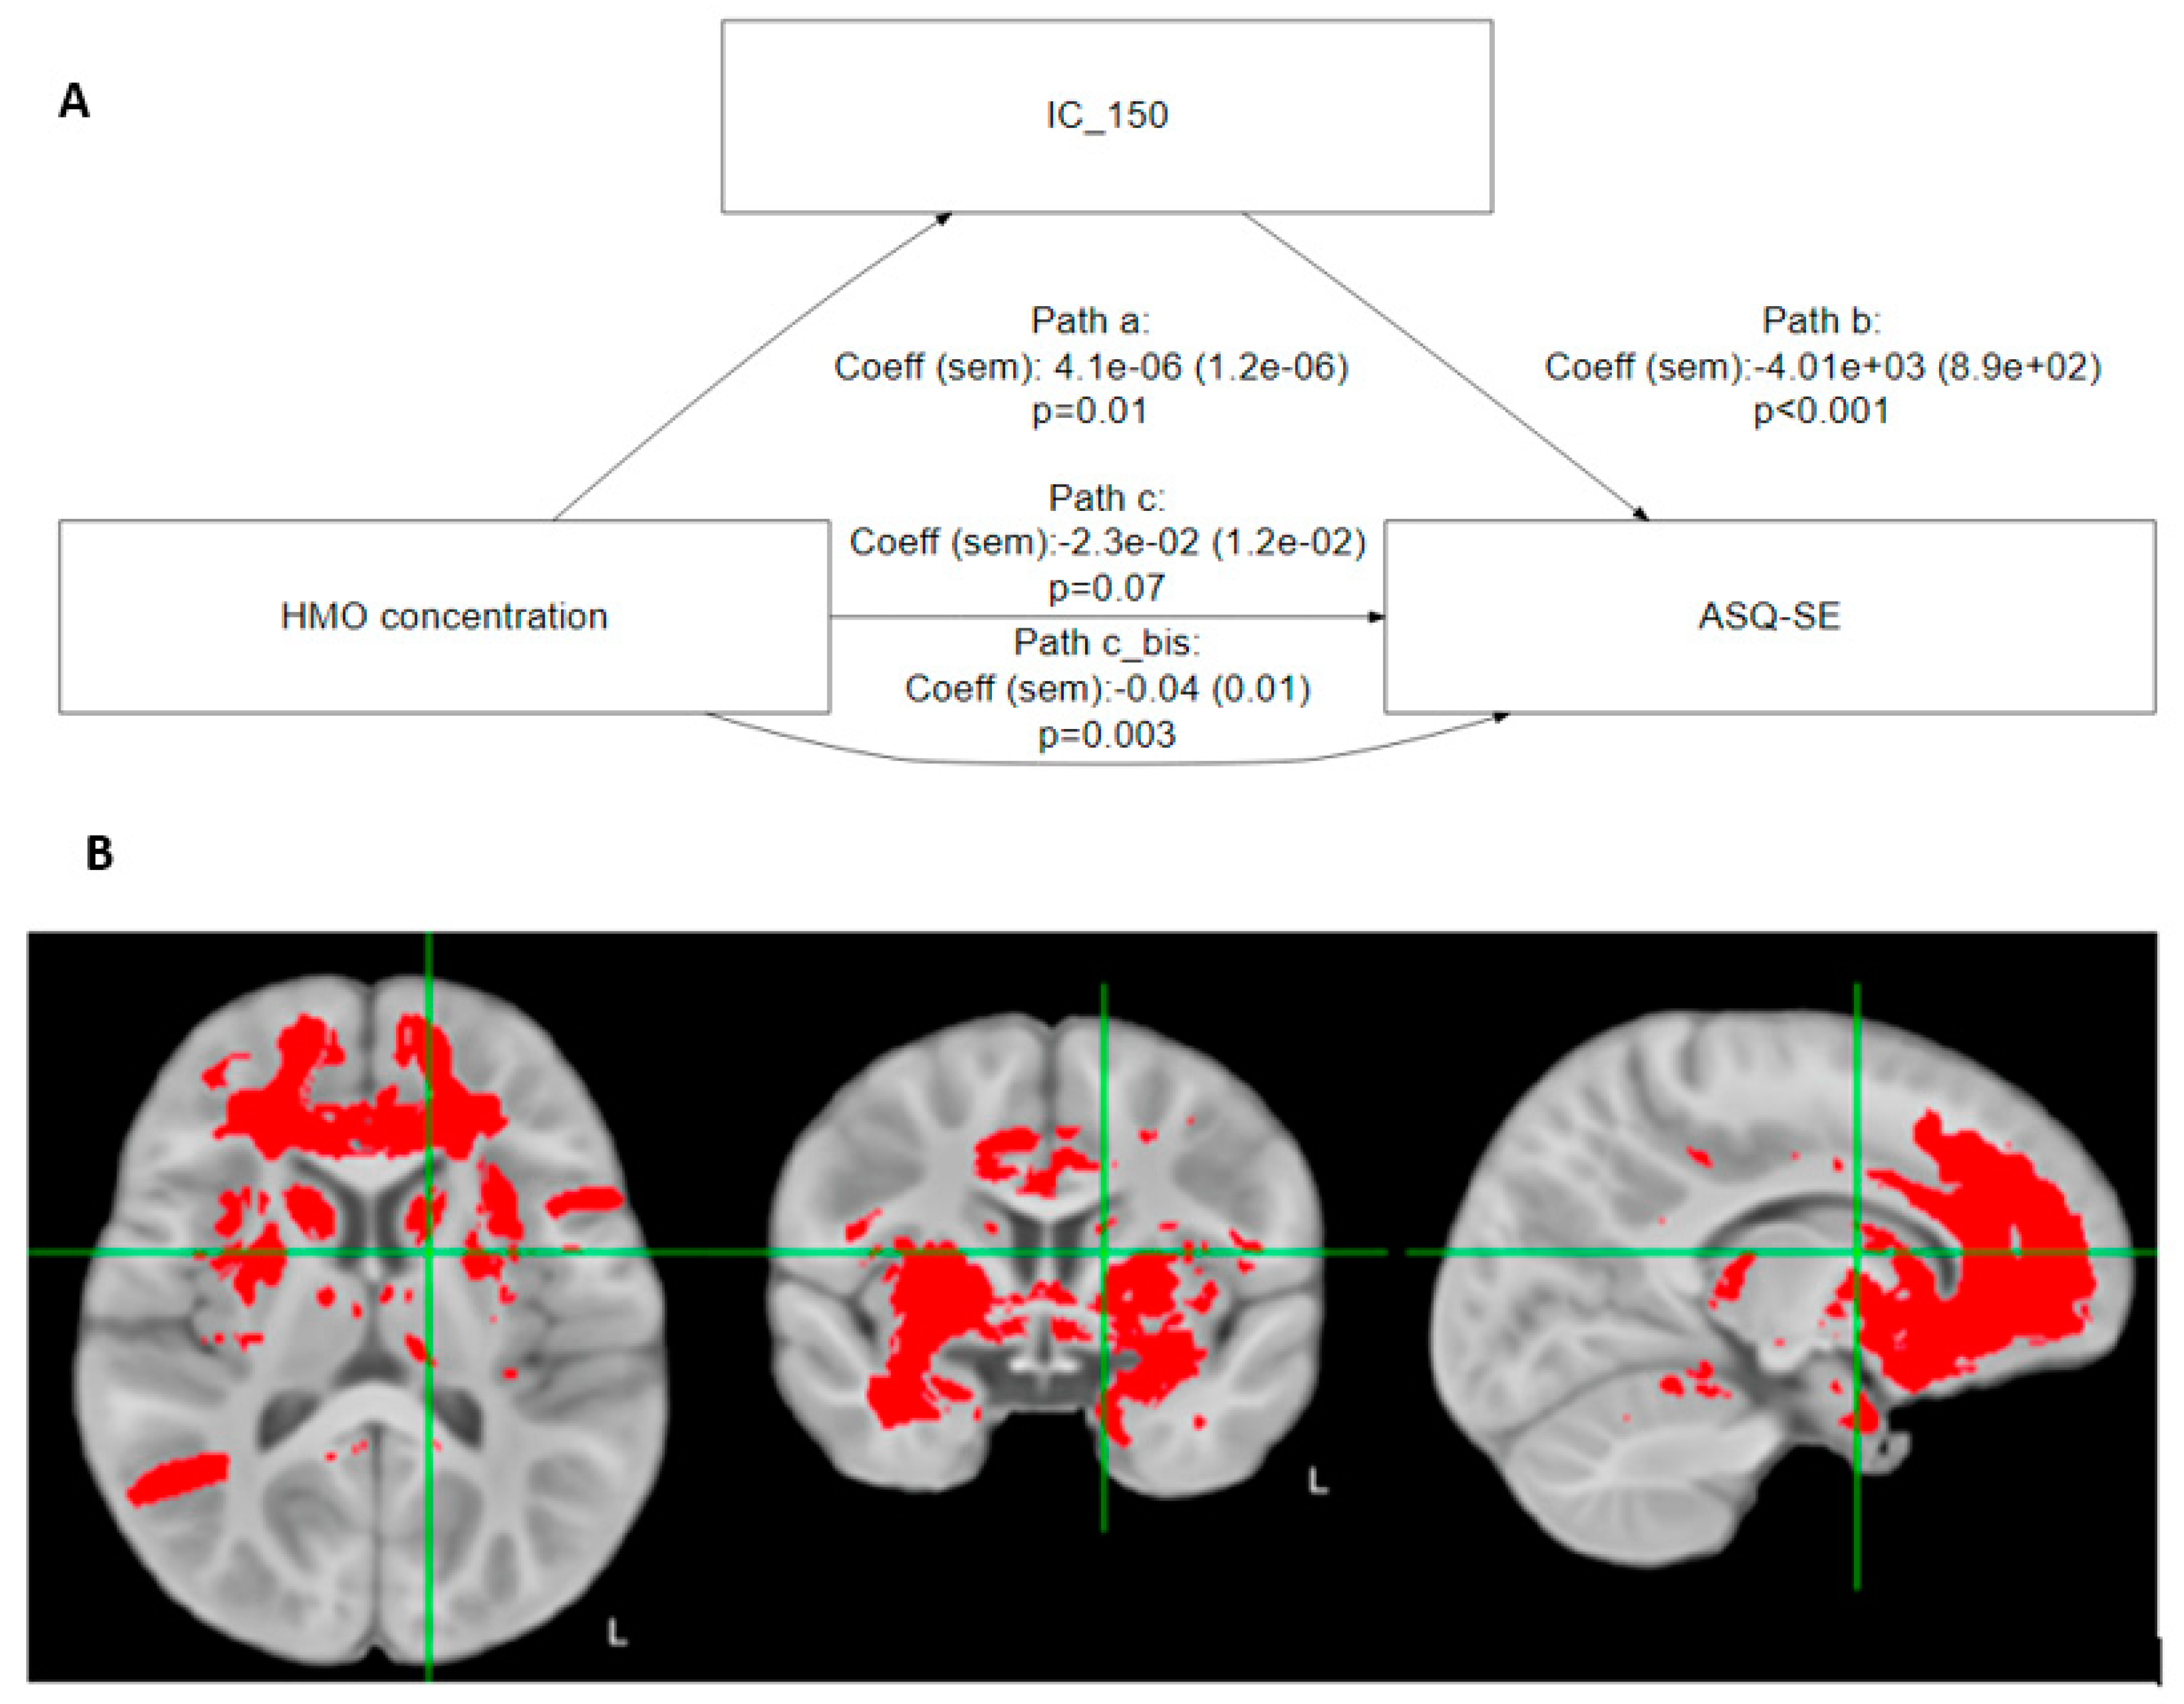

3.5. Does Myelination Mediate the Relationship between 6′SL and Social-Emotional Development?

| Independent Component | Proportion Mediated | Total Effect | ACME |

|---|---|---|---|

| IC_5 | 0.3 *** | −0.0559 *** | −0.0166 *** |

| IC_24 | 0.3 *** | −0.058 *** | −0.0193 *** |

| IC_67 | 0.6 *** | −0.0553 *** | −0.0322 *** |

| IC_74 | 0.3 * | −0.0552 | −0.0153 ** |

| IC_150 | 0.4 *** | −0.0564 *** | −0.0217 *** |

| IC_175 | 0.6 *** | −0.0574 *** | −0.0274 *** |